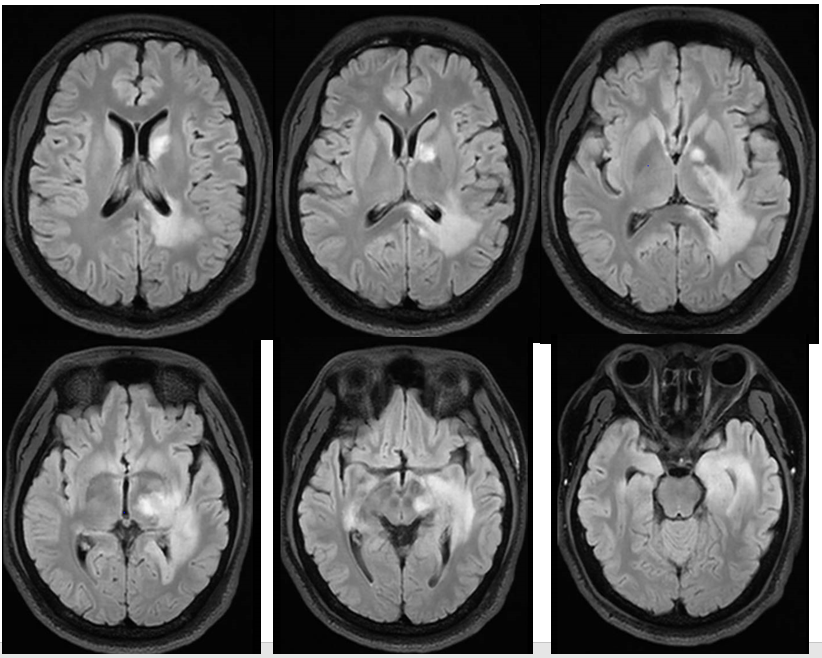

病例展示中枢神经系统脱髓鞘疾病是一

脑脱髓鞘疾病的影像诊断

脑脱髓鞘疾病的影像诊断丨影像天地